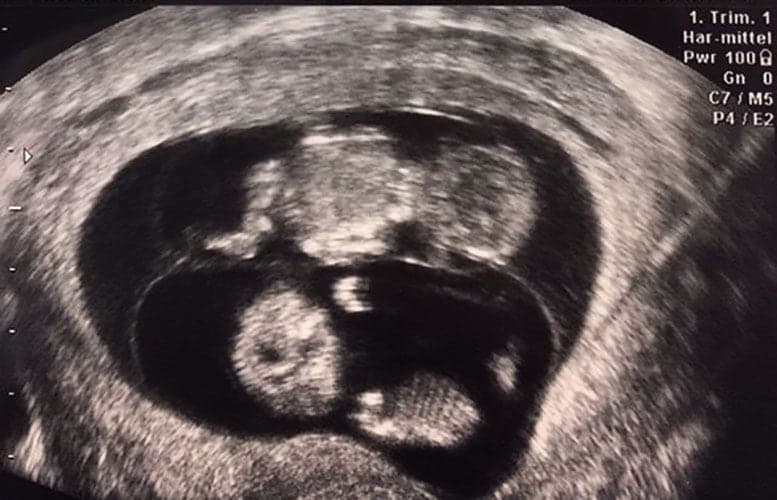

Ultraschallbilder aus dem 1. Trimester (1. SSW bis 12. SSW)

Im ersten Trimester sind die Ultraschallbilder meist noch schwer zu deuten. Oft erkennt man in den letzen Wochen des ersten Trimesters gut den Körper, den Kopf und die Gliedmaße. Das Geschlecht kann man in dieser Zeit meist noch nicht erkennen.